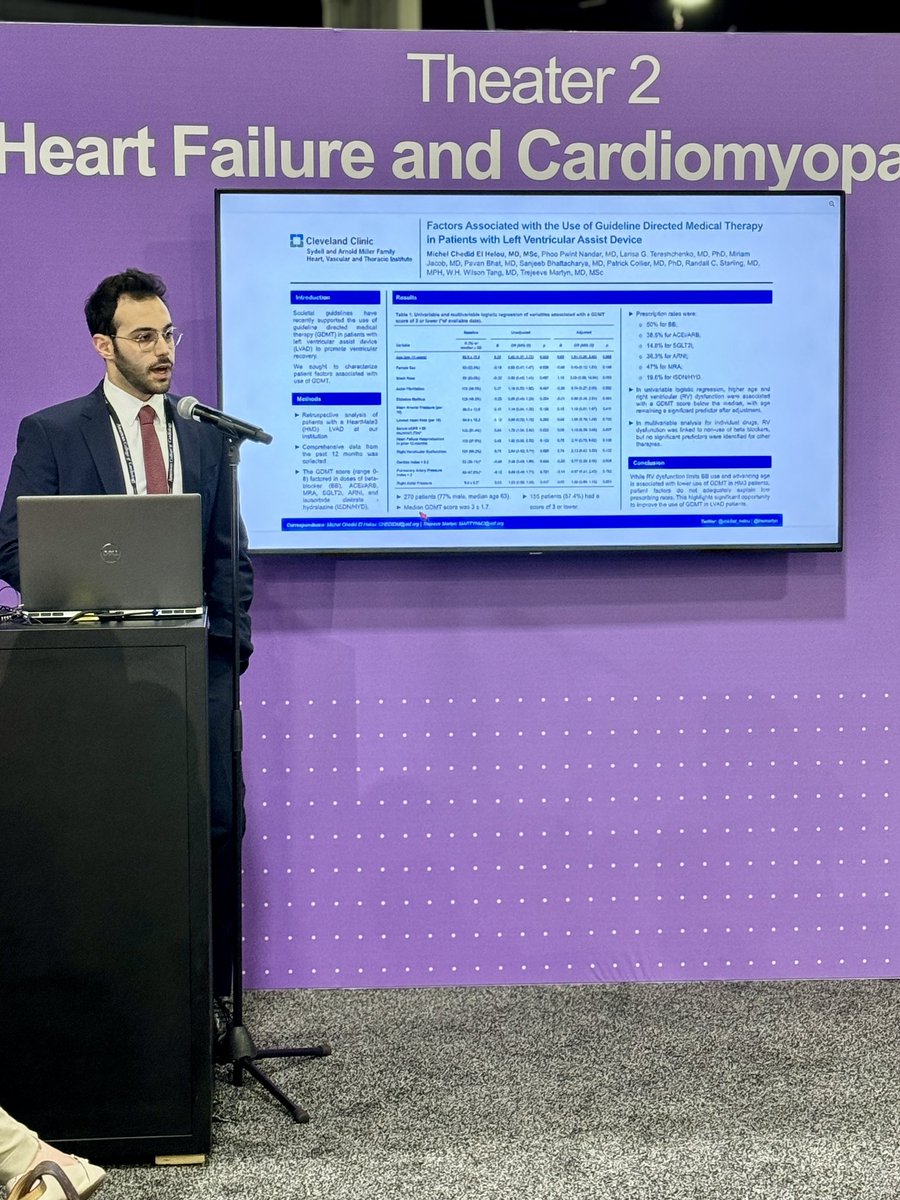

#ACC24 Day 1 at the #HeartFailure poster session, I had the honor to present our work on the use of GDMT in patients with #LVAD. Key Takeaway: ➡️ There is significant opportunity to improve the use of GDMT in LVAD patients! Trejeeve (Tre) Martyn Phoo Cleveland Clinic Heart, Vascular & Thoracic

Excited to share our work on the use of #GDMT in patients with HeartMate3 #LVAD! 🫀 Special thanks to Dr. Trejeeve (Tre) Martyn for the mentorship. Phoo Cleveland Clinic Heart, Vascular & Thoracic Read more in EJHF European Society of Cardiology Journals 👇🔗 onlinelibrary.wiley.com/doi/10.1002/ej…